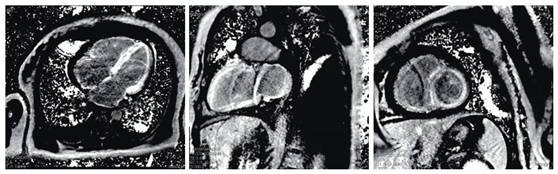

心脏MRI

心脏MRI特点

心脏淀粉样变中晚期钆强化(LGE ,late gadoliniumenhancement )极为常见,由淀粉样蛋白沉积引起的间质膨胀产生。在诊断心脏淀粉样变中具有极高的特异性。

弥漫性透壁或心内膜下LGE最为常见。相当一部分患者在LV出现形态学增厚前已存在异常LGE,因此心脏MRI具有早期检出心脏浸润的潜力。

这两个特征均可出现在心室肌和心房。